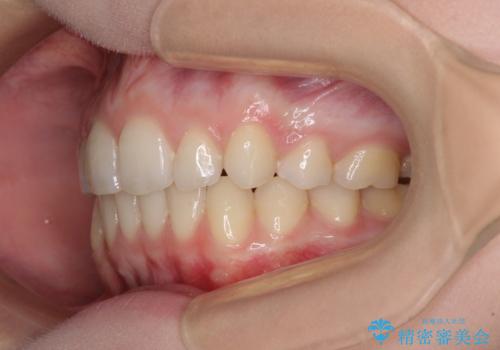

- 著しい八重歯を気にして来院された患者様です。

片側の八重歯であり上顎の正中がずれていたため、上顎左右第一小臼歯2本を抜歯して排列することとしました。

下顎の骨格的なズレが大きかったため、上下歯列のバランスが取れるか心配でしたが、上下ともに左右対称に近い歯列で治療を終えることができました。